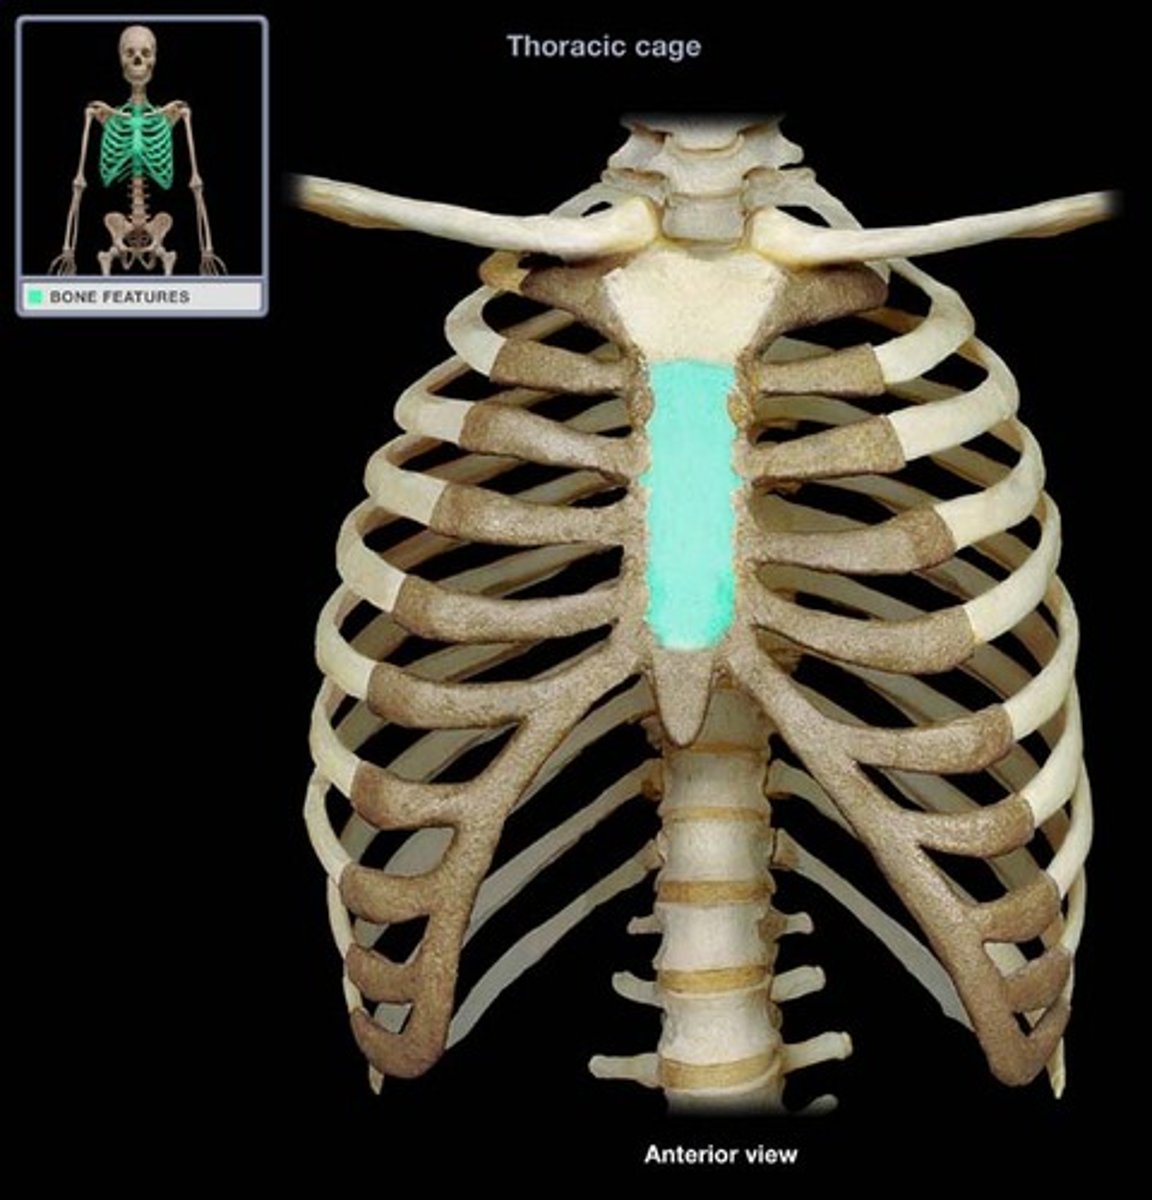

What is highlighted in blue?

Sternum(in the Sternal area)

Rib Cage (In the sternal area)

What is highlighted in blue?